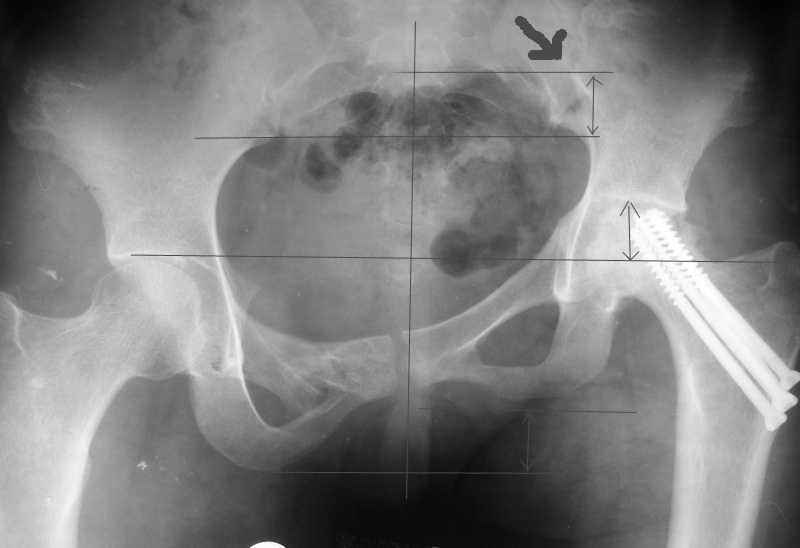

Согласен с Рунковым. Девочка молодая. Имеется ассиметричное расположение вертлужных впадин в прямой проекции. Так как повреждение таза было вертикально-нестабильное, вероятно имеется так же ассиметрия в передне-заднем направлении. Конечно протезом можно компенсировать имеющееся укорочение, но ассиметрично расположенные тазобедренные суставы приведут к нарушению двигательного стереотипа, нарушение походки, остеохондроз и т.д.

Привет, Макс. Не торопись, посмотри внимательно на истинную картину. Толстая стрелка указывает на нижний край смещенного кп сочленения.

разговоров нет, смещение значимое, какое оно было, такое и осталось. Будут проблемы и с сидением и с осанкой и т.д. Идеальным вариантом было бы, конечно, исправить деформацию, а потом запротезировать. Но... цена вопроса. сейчас деформация, судя по костной мозоли, стабильная, и таз несет основную свою функцию - опорную, явно КПС не болит. Превратить стабильную деформацию в нестабильную и потом ее исправить - задача непростая, но выполнимая. Оперативное лечение будет сложное, скорее всего многоэтапное и длительное. С определенными рисками, общехирургическими и специфическими, например несращение зоны остеотомий - нестабильный таз, ризидуальное смещение (в пределах 1 см вполне вероятно). Если считать, что на тазе укорочение см 3, остальные 5. все-таки сгибательно-приводящая контрактура. На протезе от контрактуры можно избавиться, да и см 2 удлинить за счет опила, головки. В такой ситуации решение должна принять пациентка и оно должно быть действительно информированным.